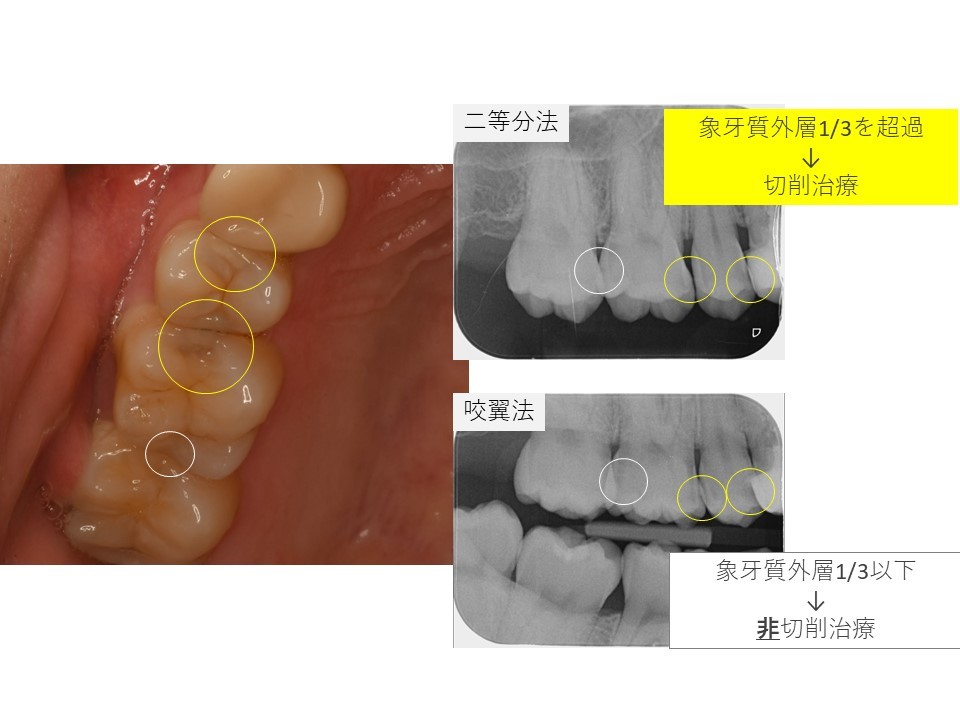

黄色の〇の場所にむし歯があります。

レントゲンを撮影します。

当院ではデンタル14枚法に加えて、咬翼法も併用して、

読影の精度を高めて、治療方法の根拠をお示ししています。

黄色〇のほかに、白い〇のところにもう蝕が確認されました。

こちらは現時点で基準以下の大きさと判断して、切削治療を選択しました。